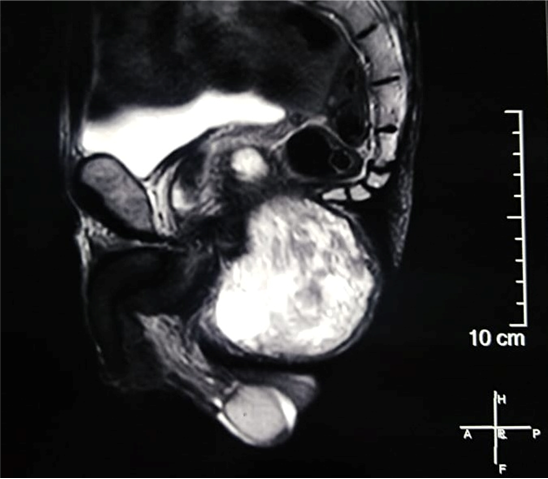

A 69-year-old male patient, consulted with complaints of swelling in the right gluteal region gradually increasing in size for 3 years, with no other associated signs. The clinical examination objected a freely mobile large mass of the right gluteal region measuring 7cmx10cm, soft, non-painful and with no inflammatory signs. There was no history of previous trauma. Magnetic resonance imaging (MRI) revealed a large, well defined mass of the right ischio-rectal pit. It showed high signal on a T2-weighted image (Figure 1), heterogeneous, iso-signal on a T1-weighted image (Figure 2), and a gadolinium-enhanced image (Figure 3), measuring 76-49-108 mm coming into contact with the internal shutter muscle outside, pushing back the anal canal into it without signs of invasion. On the basis of these radiological findings, we suspected a desmoide tumor, or liposarcoma from which the surgical indication was put. The patient was operated on with a single-block excision of the mass without capsular break-in (Figure 4-6). The surgical suites were simple. A histopathological examination revealed a well circumscribed mass composed of a mixture of mature adipocytes and spindle cells in varying proportions surrounded by a clear fibrous capsule. Neither the lipomatous nor the spindle cell elements of the tumors showed evidence of necrosis or mitotic activity. The immune histochemical analysis, showed that the lesional spindle cells were strongly immunoreactive for CD34 and the results of MDM2 immunostaining were negative. The diagnosis of SCL of the gluteal region was concluded.

Figure 1 Sagittal section of Pelvic MRI showing a mass with high signal on a T2 weighted image.